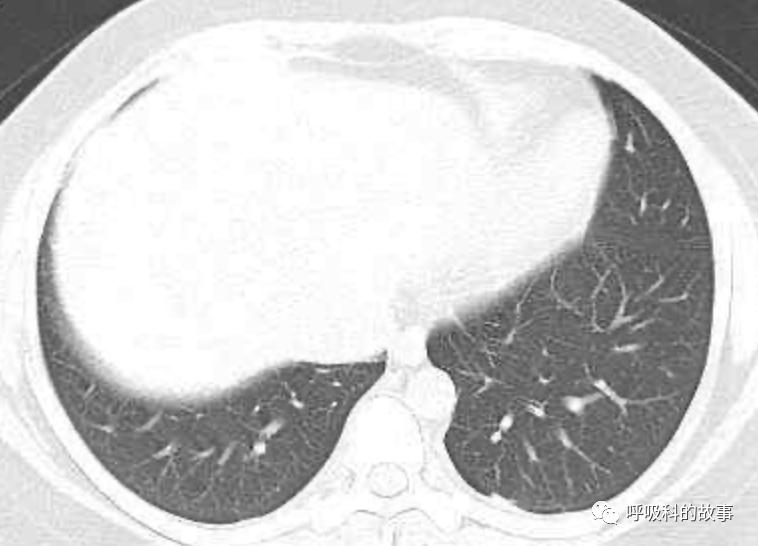

患者发热后行胸部CT检查(6月21日,住院第13天),可见两下肺有条片影,当时考虑是肺炎引起的发热。

可是在6月26日(往院第18天)仍持续发热的情况下复查肺部CT,肺部病灶已明显吸收了。那么患者发热的原因到底是什么呢?为什么患者高热的情况下血白细胞不升反降,C反应蛋白也没有明显增高?这个时候消化科医生也迷茫了,这可怎么办?于是请感染科和呼吸科医生一起会诊,共商计策。